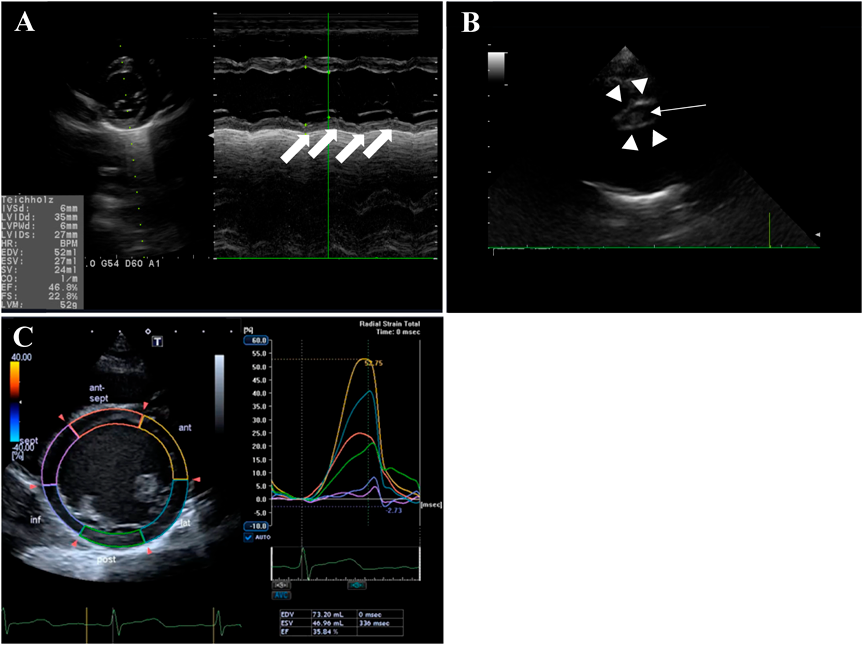

Electrocardiography (ECG) showed sinus rhythm with deep Q in III and aVF, ST elevation in I and V1, and ST depression in V2–V6 (Fig. 1). Echocardiography revealed impairment of the left ventricle (LV), with LV ejection fraction (LVEF) of 46.8% (Fig. 2A). The patient was admitted to the PICU on suspicion of acute myocarditis, and 3 µg/kg/min dobutamine and 0.5 µg/kg/min milrinone were started. Laboratory data were: WBC: 12.900/µL; RBC: 443×104/µL; Hb: 12.5 g/dL; PLT: 29.8×104/µL. Renal function, electrolytes, and standard coagulation values were within normal limits. Serological markers of myocardial damage were unremarkable: GOT: 30 U/L; LDH: 248 U/L; CPK: 149 U/L; CK-MB: 23 U/L; TnT: 0.025 ng/mL; NT-pro BNP: 166 pg/mL; BNP: 20.7 pg/mL.

Fig. 2 (A) Echocardiography showed reduced wall motion in the inferior-posterior area of the LV (arrow). (B) Echocardiography revealed severe dilatation of the right coronary artery (RCA) (7.4 mm, Z+9.1) (arrowhead) with a low echoic lesion suggesting thrombosis (arrow). (C) 2DST revealed low radial strain in the inferoseptal and inferior areas

2DST, two-dimensional speckle tracking.

Re-echocardiography in the PICU revealed severe dilatation of the RCA (7.4 mm, Z+9.1) with a low echoic lesion suggesting thrombosis (Fig. 2B) and reduced wall motion in the inferior-posterior area of the LV (Fig. 2A). Echocardiography with two-dimensional speckle tracking (2DST) revealed low radial strain in the inferoseptal and inferior areas (Fig. 2C). Circumferential and longitudinal strain were also low in the same areas. Multi-low detector computed tomography (MDCT) showed occlusion of the RCA at the #2 segment due to thrombus formation with aneurysmatic dilatation of about 2.0 cm in length and 7.0 mm in diameter. The distal segments of the RCA (#3, #4) provided contrast (Fig. 3).